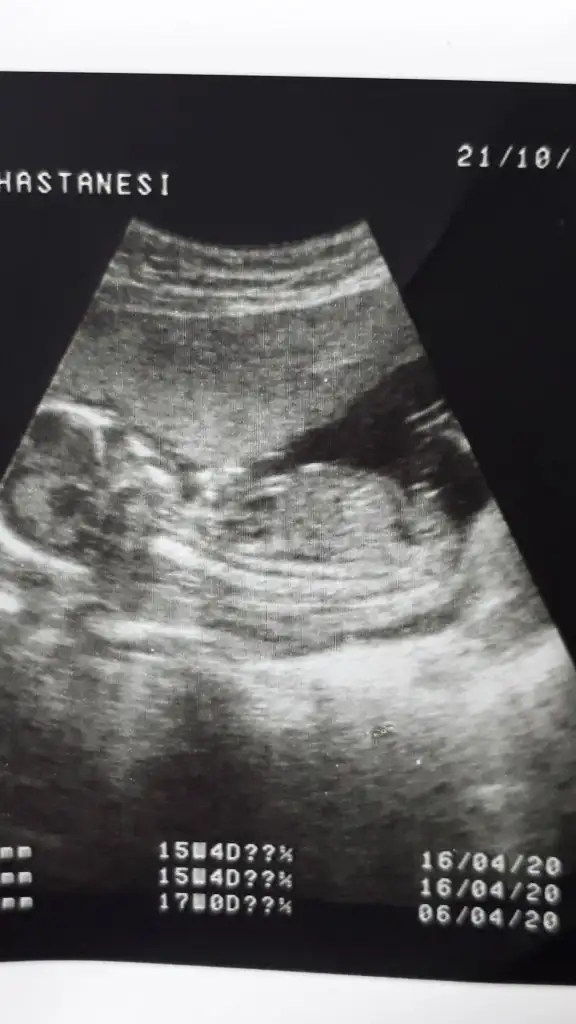

Kizlar benim bebegim erkek. Tum ultrasonlarini attim. Sirasi biraz karisti sanirim. Siz bakip tum teorilere gore karar verin. Nub dan baskasi dogru degil sanki he?

Ramziye gore kiz demislerdir kesin saga yakin bebek diye.

Iste yurt disinda Ramzi teorisi bebegin saga yakinligi diil plasentanin konumuna göre yapiliyor.

Yanlis yapiyorlar analizi buradakiler.

Hayirli olsun bu arada.

Nub teorisinde erkek yorumlamıştım usgnizi